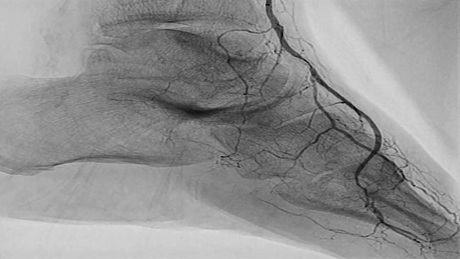

Peripheral Rotablator™

Rotational Atherectomy System

Case Studies